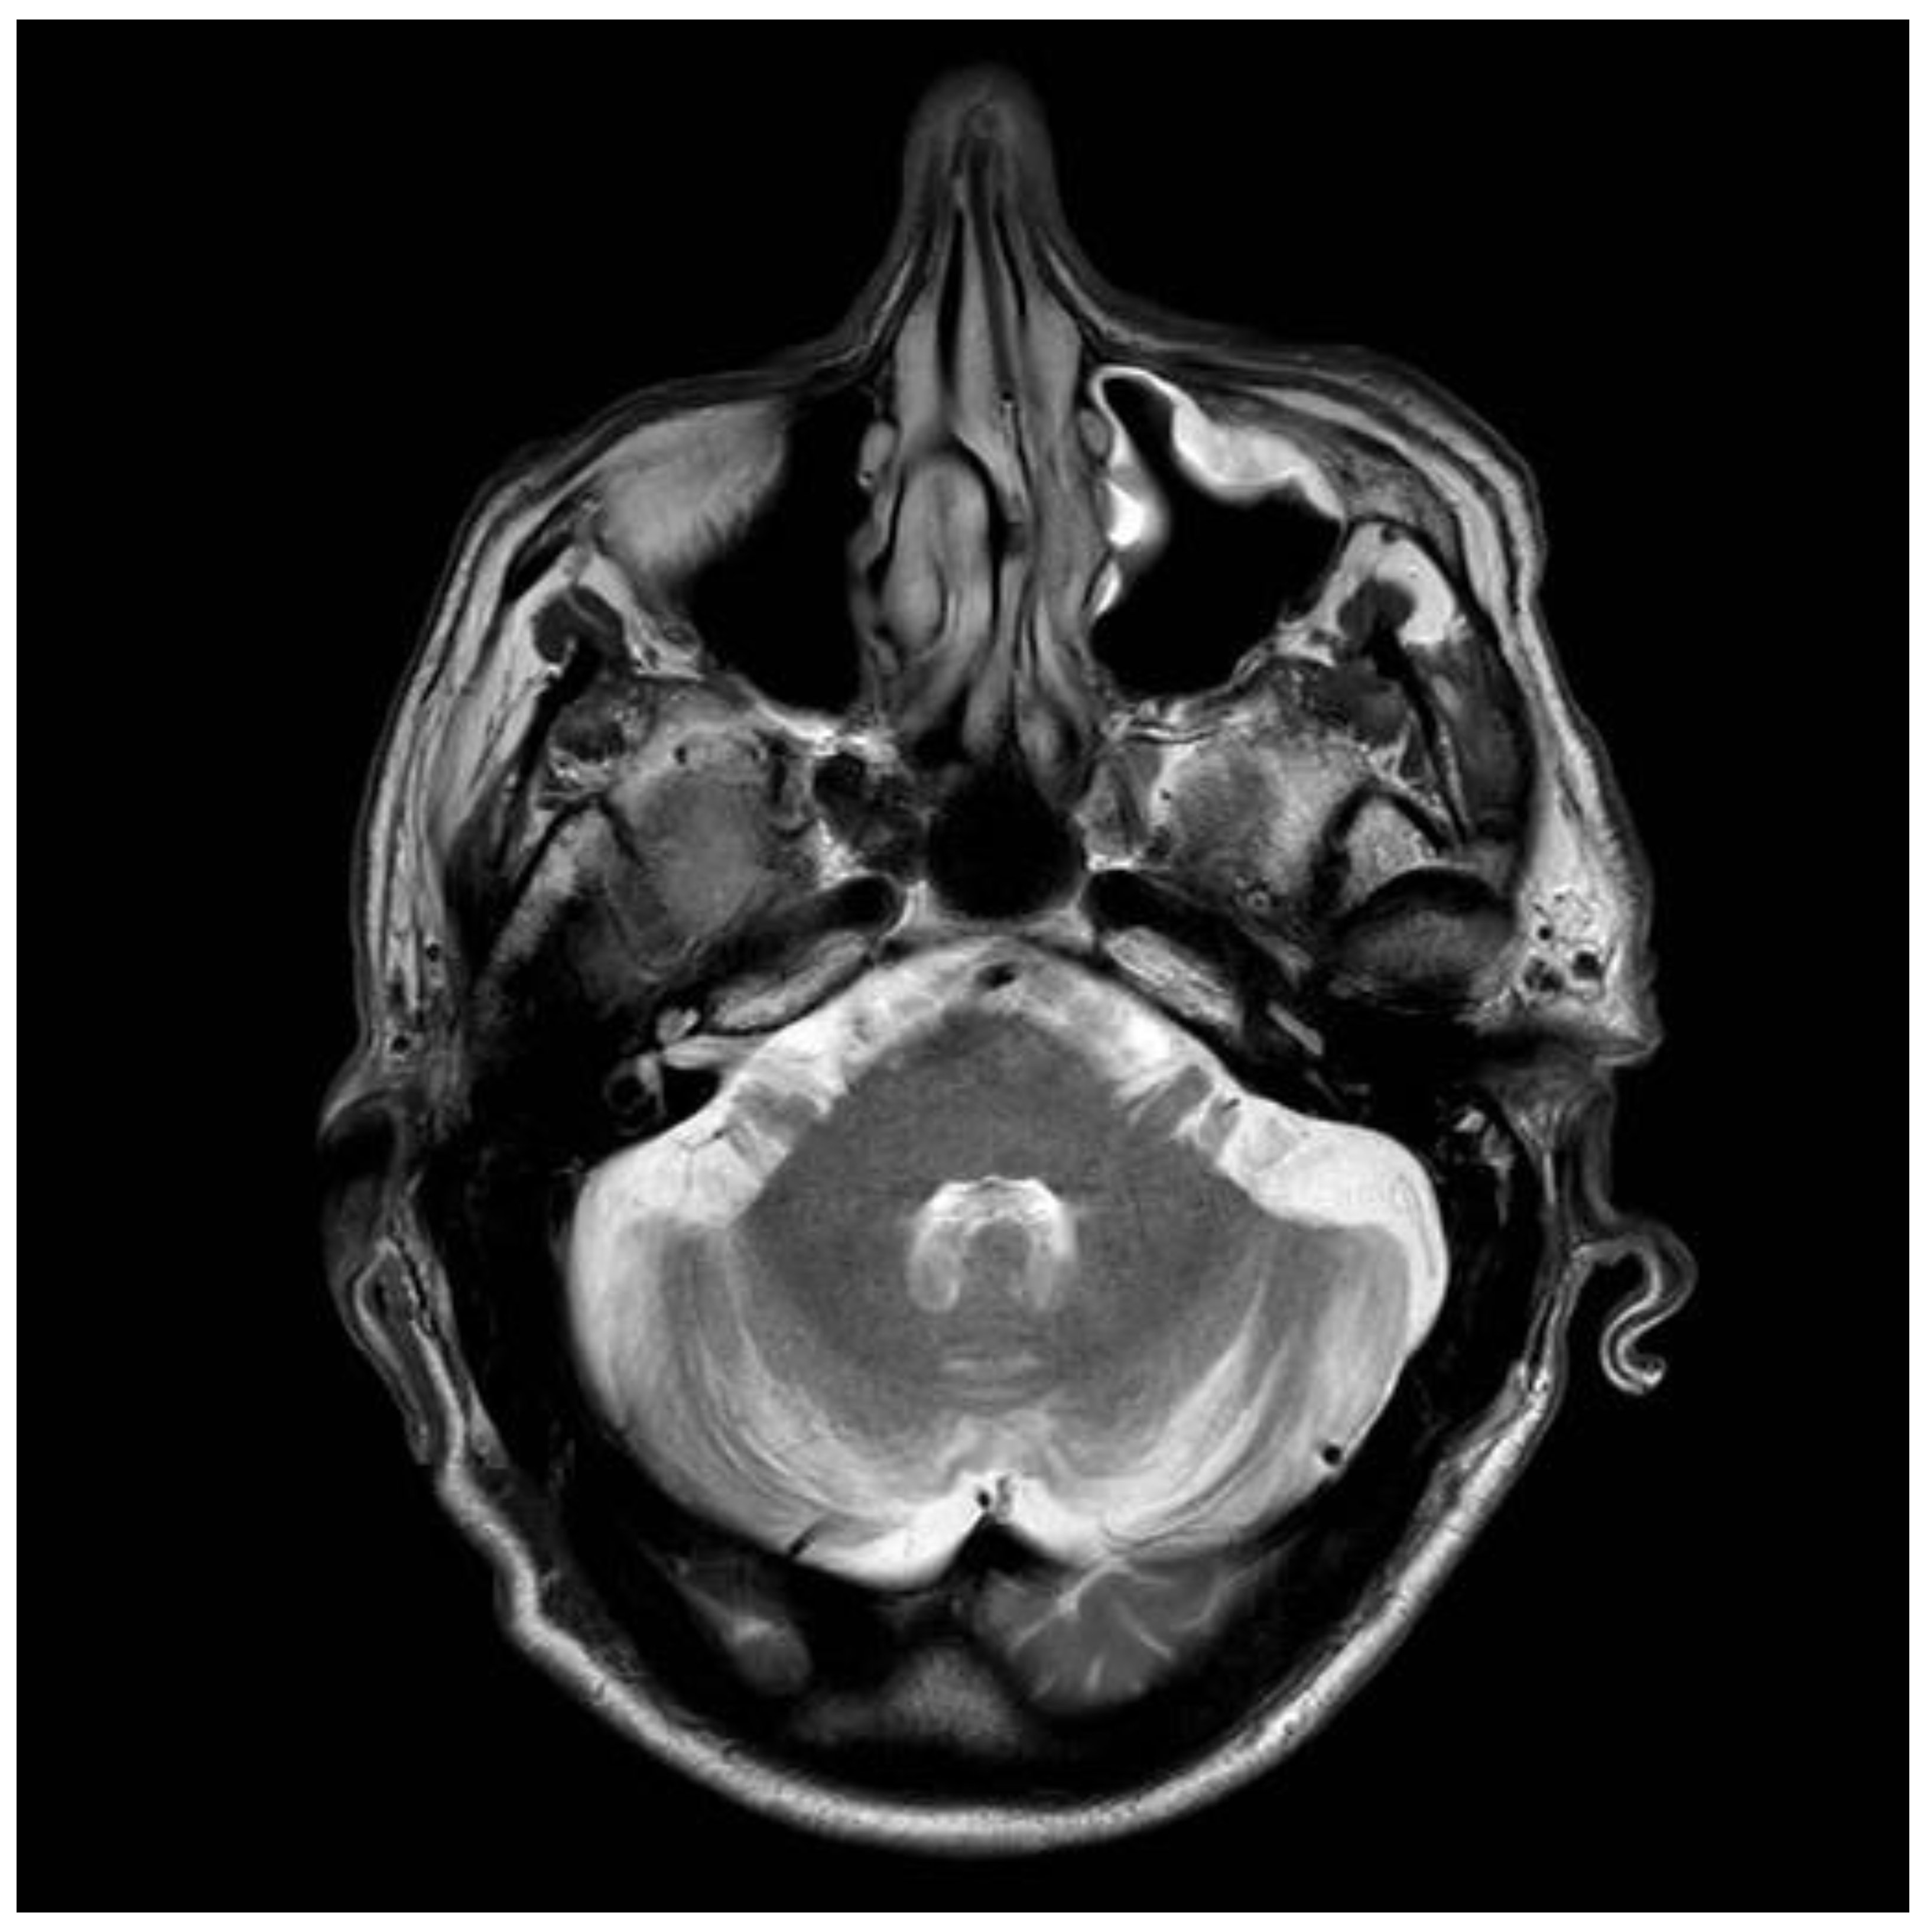

Figure 3. Brain Magnetic resonance imaging (MRI) scan conducted on presentation in 1997. The patient was diagnosed with gluten encephalopathy, having presented with headaches and cognitive difficulties. Serological testing and subsequent duodenal biopsy confirmed celiac disease (CD). The scan shows white matter changes typical of what is seen in the context of gluten encephalopathy.

Figure 4. Brain MRI scan conducted on the same patient, as in Figure 3. The scan was conducted in 2018 and at that point showed evidence of cerebellar atrophy that apparently developed over an interval of 21 years. The patient now displays clinical evidence of cerebellar ataxia.

4. Predictive Value of Different Transglutaminase Antibodies: An Illustrative Case

A 41-years old man presented to neurology in 1997, with intractable headaches for the previous 2 years. He described them as severe, often unilateral and throbbing, lasting for several days and often associated with focal but transient neurological deficits (e.g., hemisensory disturbance and double vision). He also complained of memory difficulties and inability to concentrate. Brain MRI was done to rule out any ischemic cerebrovascular events. This showed white matter changes not typical of stroke or inflammation but of undetermined clinical significance (Figure 3). He had no vascular risk factors. He was started on aspirin and discharged. Subsequent outpatient clinical review showed ongoing symptoms of headache, and poor concentration and compromised memory function interfering with his everyday activities. Additional investigations at that stage ruled out systemic lupus erythematosus (SLE) and antiphospholipid syndrome. Cardiac echo and 24-h cardiac recordings, as well as vascular imaging were normal. Blood tests (available at that time) found him to be positive for anti-gliadin (AGA) and EMA antibodies. Duodenal biopsy confirmed the presence of gluten-sensitive enteropathy. It was thought that the headaches and MRI changes were secondary to CD (gluten encephalopathy) [12]. The patient was given advice for GFD by an experienced dietitian. He was followed up at regular intervals (every six months). Initial review after being on the diet for 6 months showed significant improvement in his headaches and cognitive difficulties. His adherence to the GFD over subsequent years was intermittent for a number of reasons—he could not afford gluten-free products, family problems and housing issues, and a one-year spell in prison. During this period, his antibody profile remained positive. He continued to be reviewed by the dietitian and attempts were made to ensure strict adherence to GFD. In 2006, he completely abandoned the GFD, but he restarted it a year later. He gave up the diet again in 2009. A few months later, he presented with an itchy vesicular rash over his arms and face. Dermatological review and skin biopsy confirmed the diagnosis of DH. He was still consuming gluten and serological testing for TG2 IgA, EMA, and anti-gliadin antibodies confirmed the presence of CD-related antibodies. He remained symptomatic with frequent headaches. More recently, he developed a degree of gait incoordination and a tendency to fall. He also complained of distal sensory disturbance with a burning feeling in his feet, less so in his hands. Further brain imaging showed evidence of cerebellar atrophy (Figure 4) that was not present in the baseline scan. Neurophysiological assessment including thermal threshold studies confirmed the presence of small fiber neuropathy.

Serum from this patient was stored at the time of the diagnosis of gluten encephalopathy (1998), and was subsequently available for testing for TG2, TG3, and TG6 autoantibodies, when these serological tests became available [7,13]. The tests showed him to be positive for deamidated gliadin peptide antibodies (IgA/IgG) and, interestingly, all 3 types of transglutaminase autoantibodies (TG2 IgA/IgG, TG6 IgA, and TG3 IgA/IgG). The TG2 antibody positivity would be expected on the basis of CD. TG6 antibody positivity would be in keeping with the diagnosis of gluten encephalopathy and the subsequent development of cerebellar ataxia (gluten ataxia) and neuropathy (gluten neuropathy), due to poor adherence to a GFD. The positive anti-TG3 antibody result from the 1998 sample would explain the subsequent development of DH, which however, manifested in 2009, over 10 years after the initial presentation with the neurological complaints. The patient is still under regular review and during his last attendance (August 2020) he tested positive for TG2, EMA, AGA, and TG6 IgG and IgA antibodies. AGA and TG2 antibodies were tested throughout his clinic appointments and were always positive. An observed reduction of the TG2 titer was only seen in 2008 and 2016, whilst he was trying to be strict with his GFD.